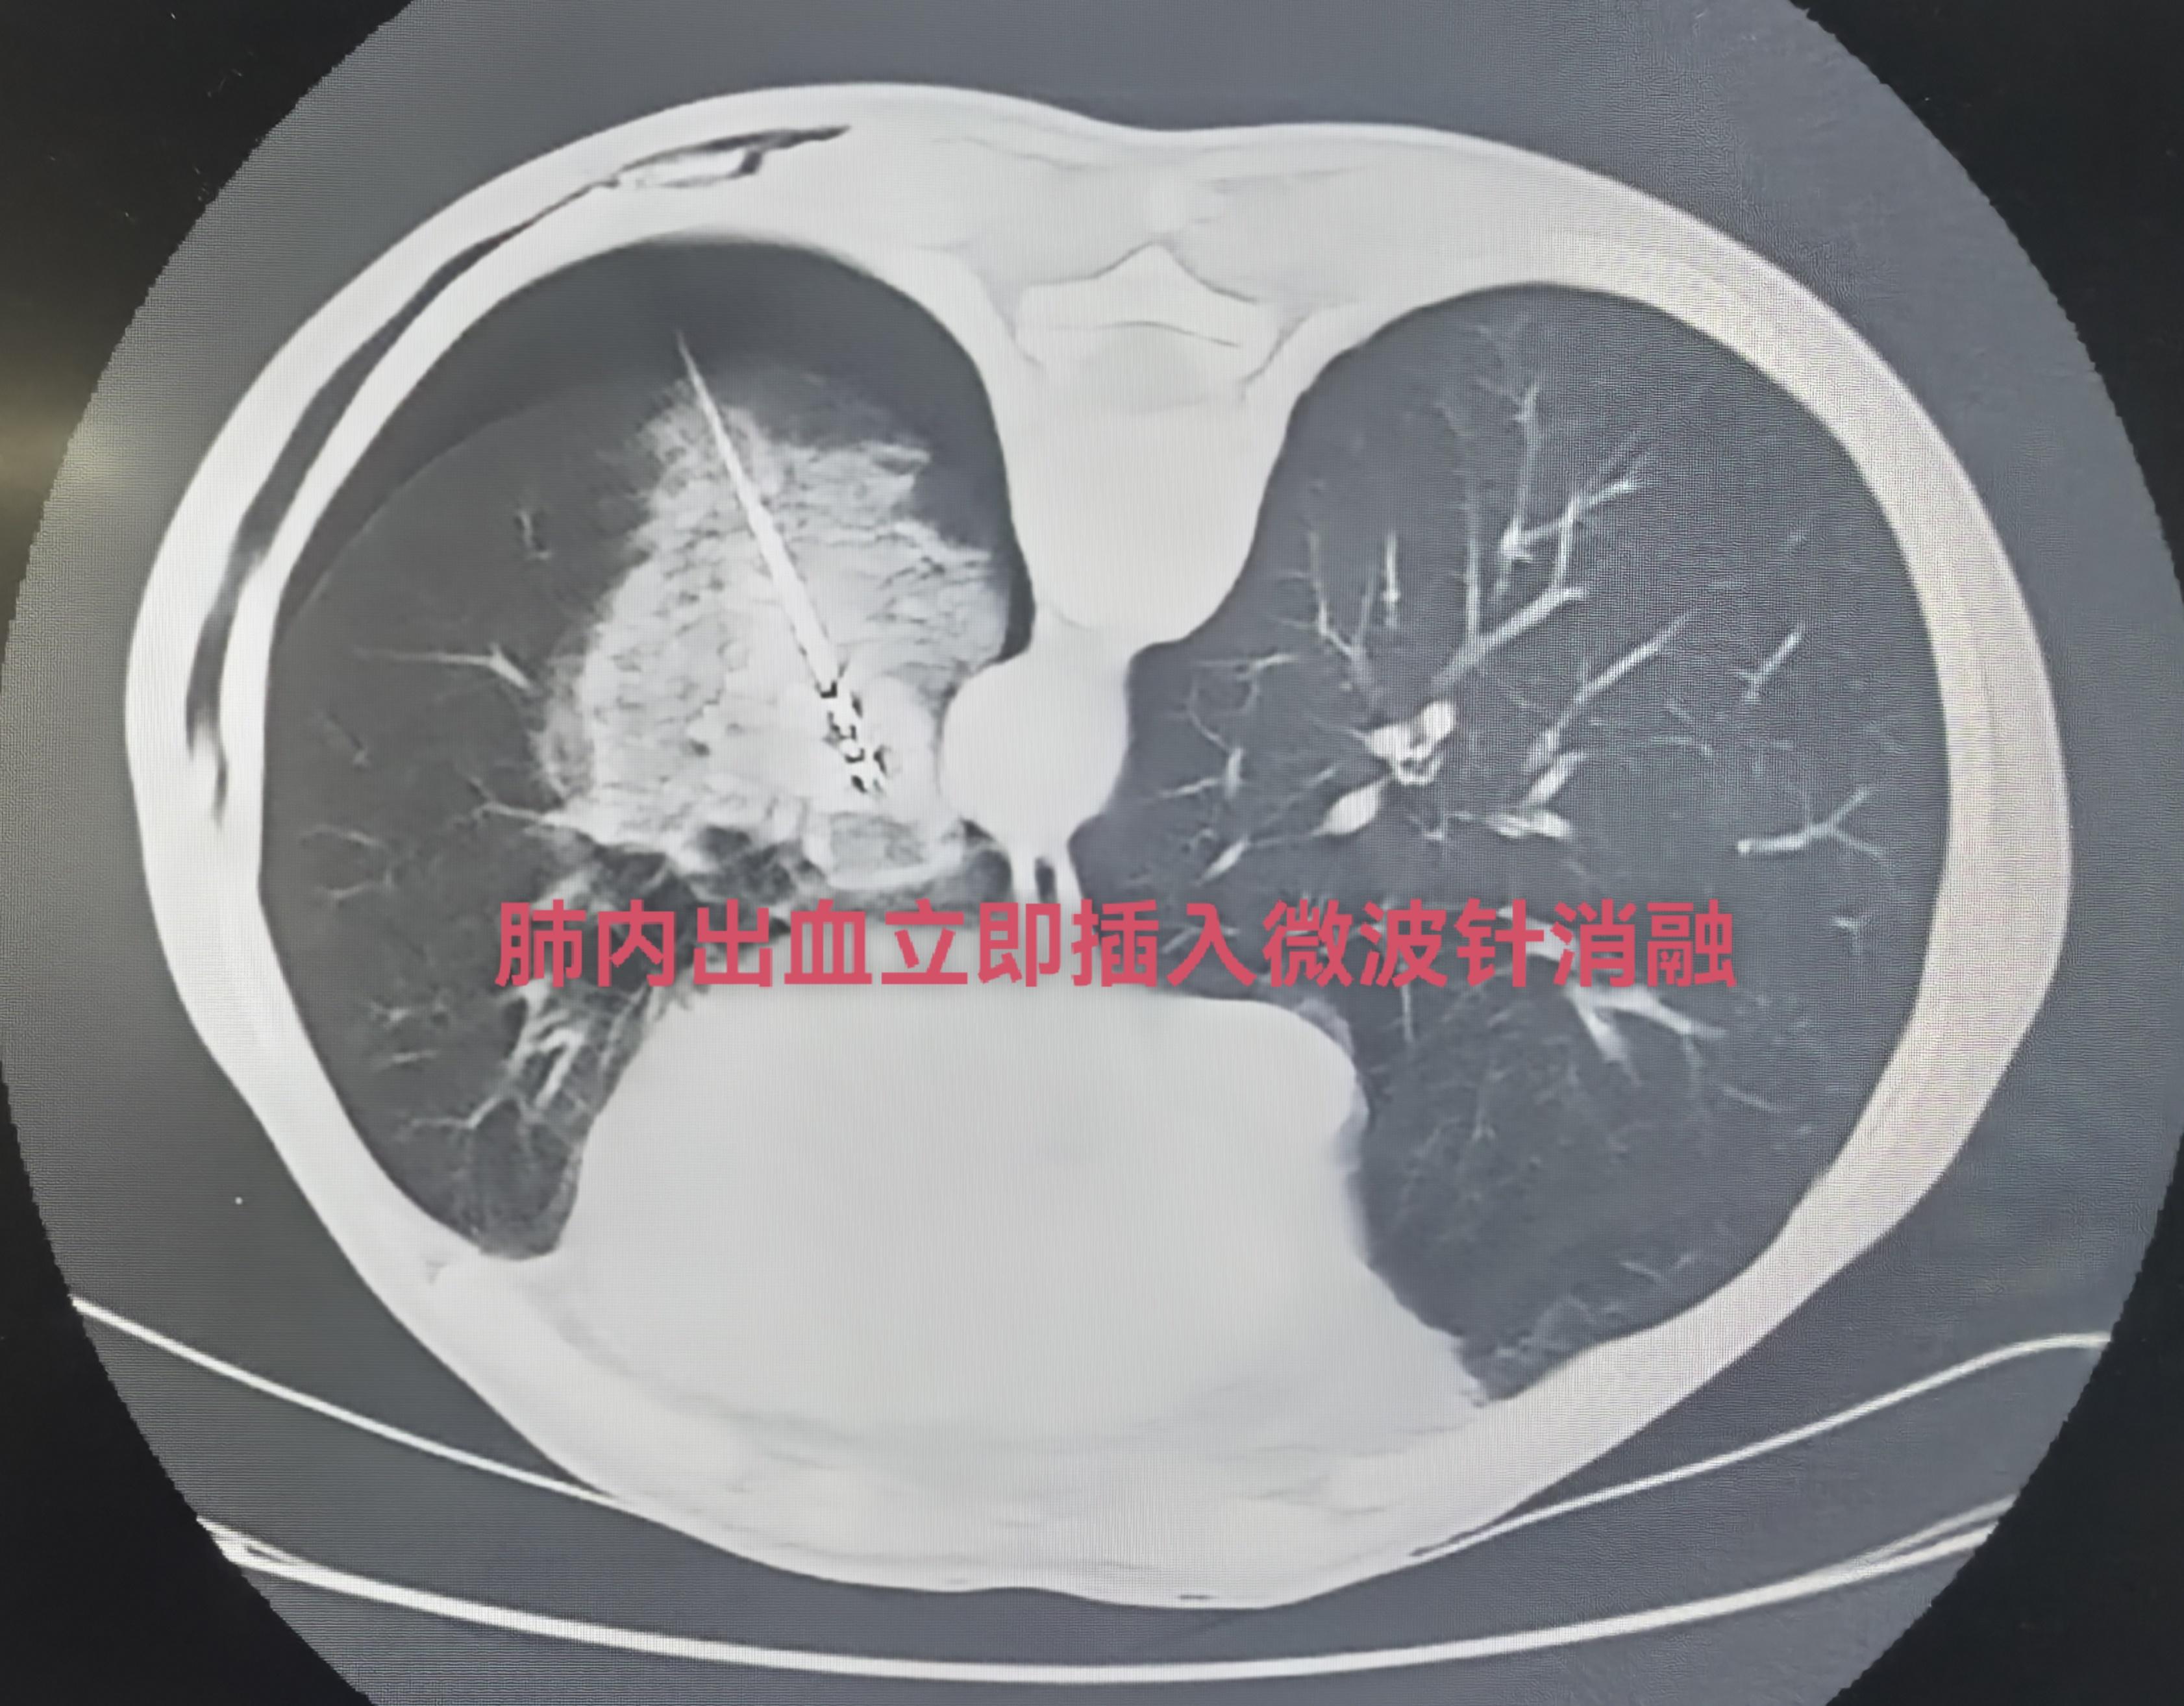

一例肺转移瘤微波消融: 3天前一台直肠。一例肺转移瘤微波消融: 3天前一台直肠癌术后肺寡转移(直径3cm)紧贴胸主动脉行CT引导下微波消融术,术后复查“煎蛋征”完全覆盖肿瘤,肿瘤完全灭活。微波消融微创介入治疗,创伤小恢复快,安全有效。